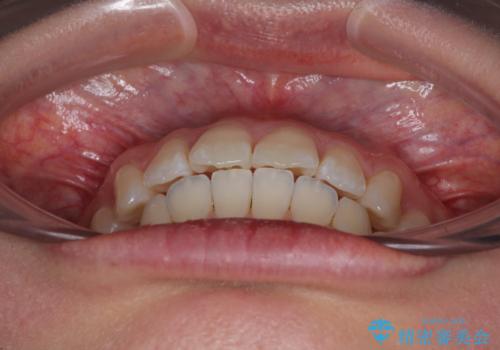

深い咬み合わせによる隙間 インビザライン矯正でコンプレックスを改善

- 上の前歯の隙間を気にして来院された患者様です。

インビザラインにより、上下の歯列を側方に拡大しつつ、前歯の隙間を閉じていくこととしました。

隙間の原因は強い咬合力や舌の突出癖、小帯の異常付着などがありますが、舌のトレーニングをしっかりと行いながら、装着時間を遵守して装着していただいたおかげで、スムーズに治療を終えることができました。